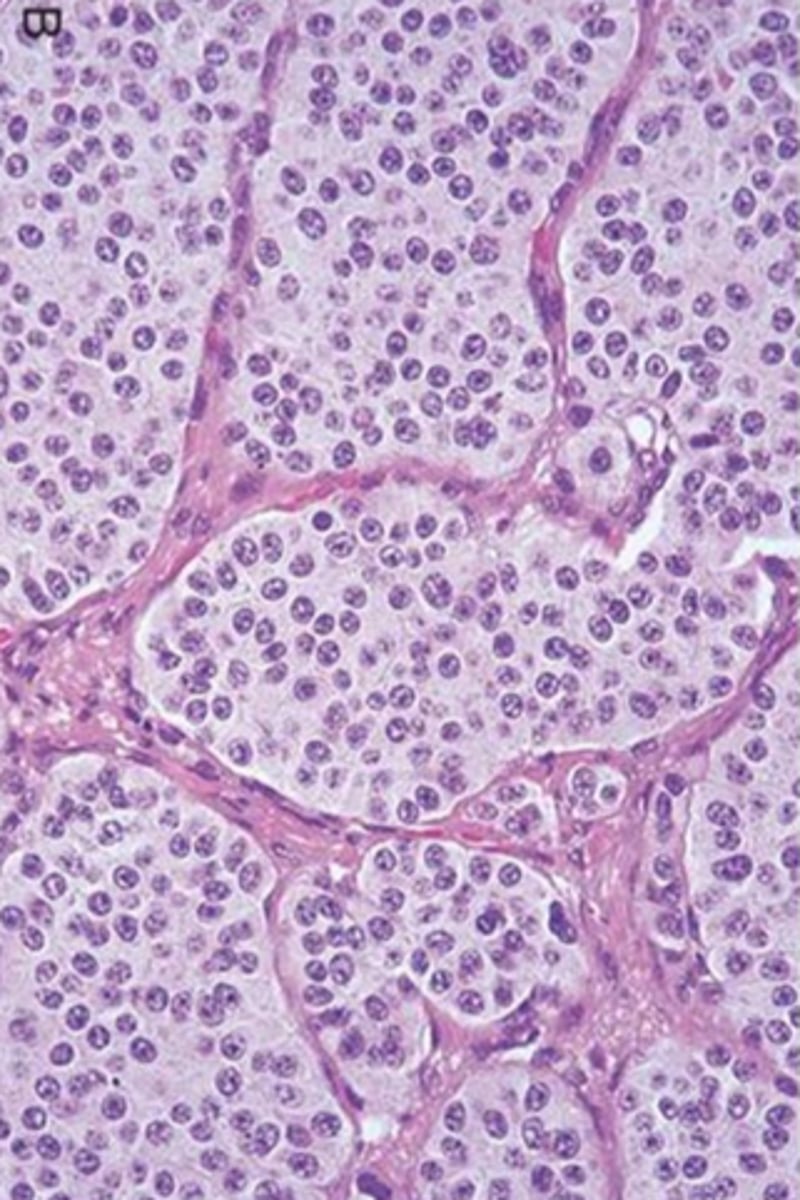

Dry eyes, dry mouth, arthritis, recurrent dental caries

Sjogren syndrome

(autoimmune destruction of exocrine glands)

Can have RF, Anti-SSA or SSB

Lymphocytic sialadenitis

Risk of B-cell lymphoma